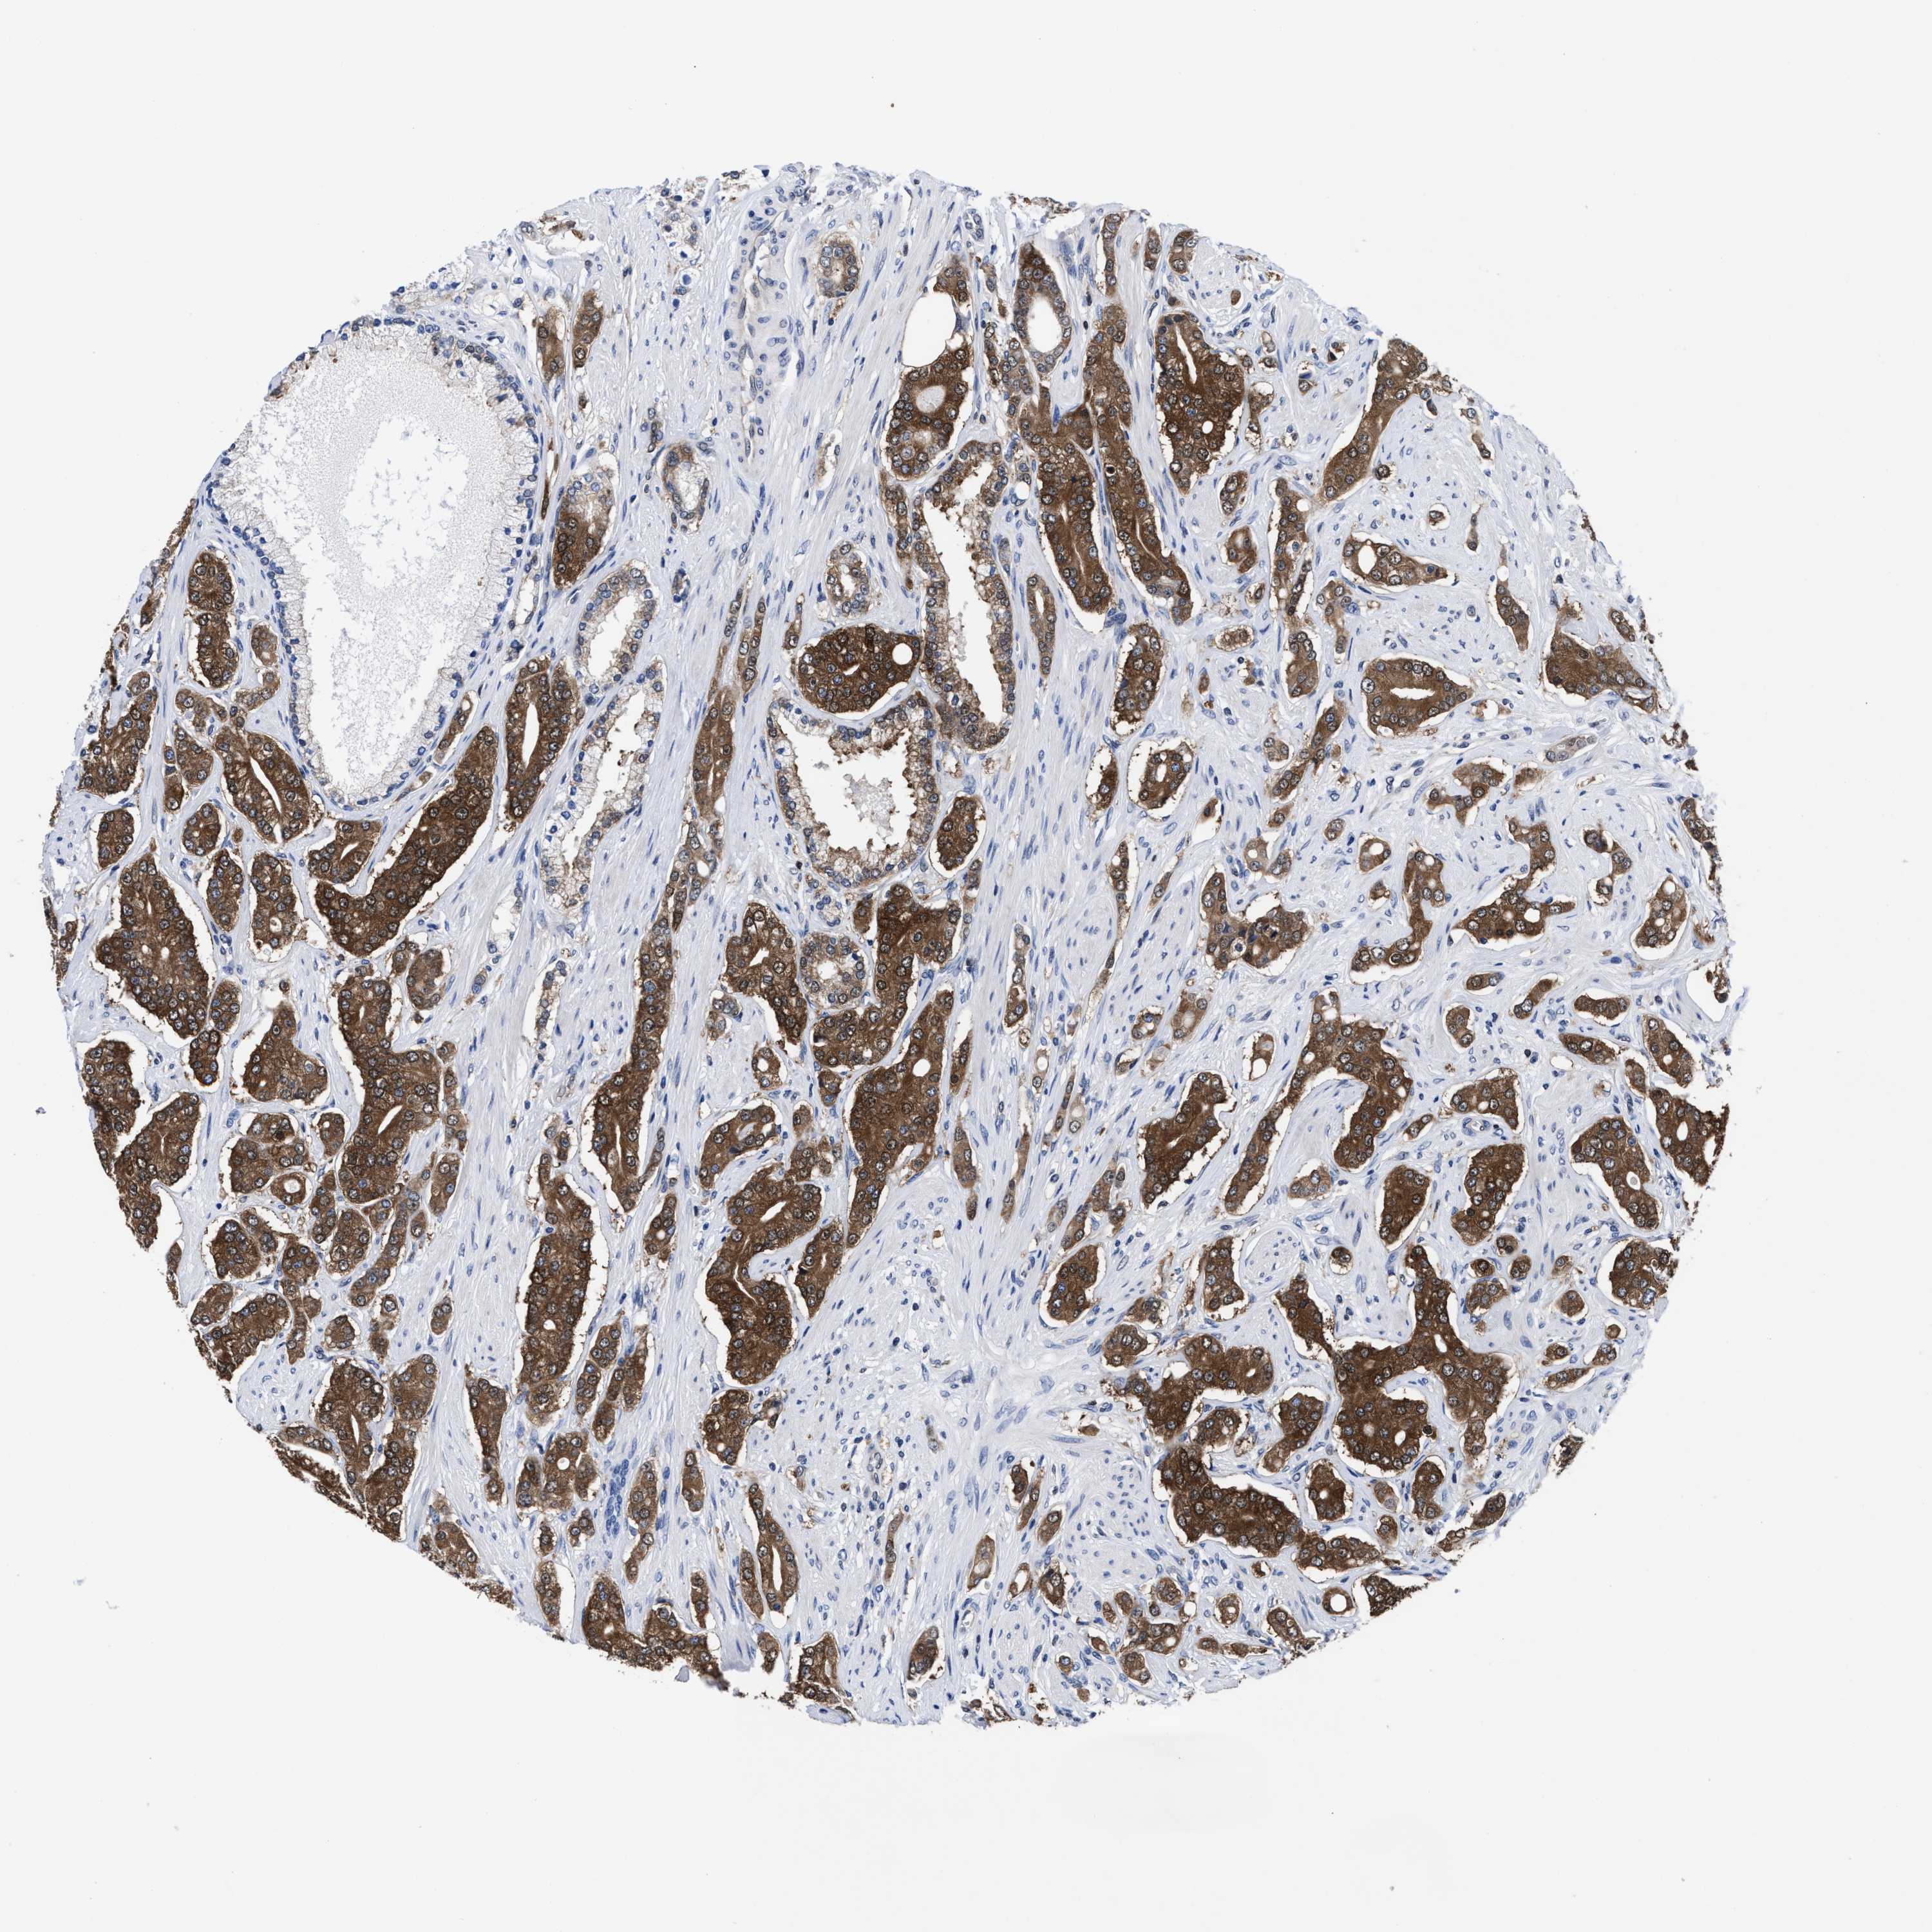

PROSTATE CANCER - Protein expressioni

A mouse-over function shows sample information and annotation data. Click on an image to view it in a full screen mode. Samples can be filtered based on level of antibody staining by selecting one or several of the following categories: high, medium, low and not detected. The assay and annotation is described here.

Note that samples used for immunohistochemistry by the Human Protein Atlas do not correspond to samples in the TCGA dataset.

Antibody stainingi

Antibody staining in the annotated cell types in the current human tissue is reported as not detected, low, medium, or high, based on conventional immunohistochemistry profiling in selected tissues. This score is based on the combination of the staining intensity and fraction of stained cells.

Each image is clickable and will lead to virtual microscopy that enables deeper exploration of all samples and also displays staining intensity scores, fraction scores and subcellular localization as well as patient and tissue information for each sample.

HPA022434

HPA022953

HPA022959

HPA028758

CAB007783

Adenocarcinoma, High grade

Adenocarcinoma, Low grade